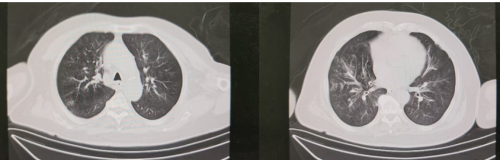

胸部CT(11-14):考虑支气管炎。双肺散在炎症。